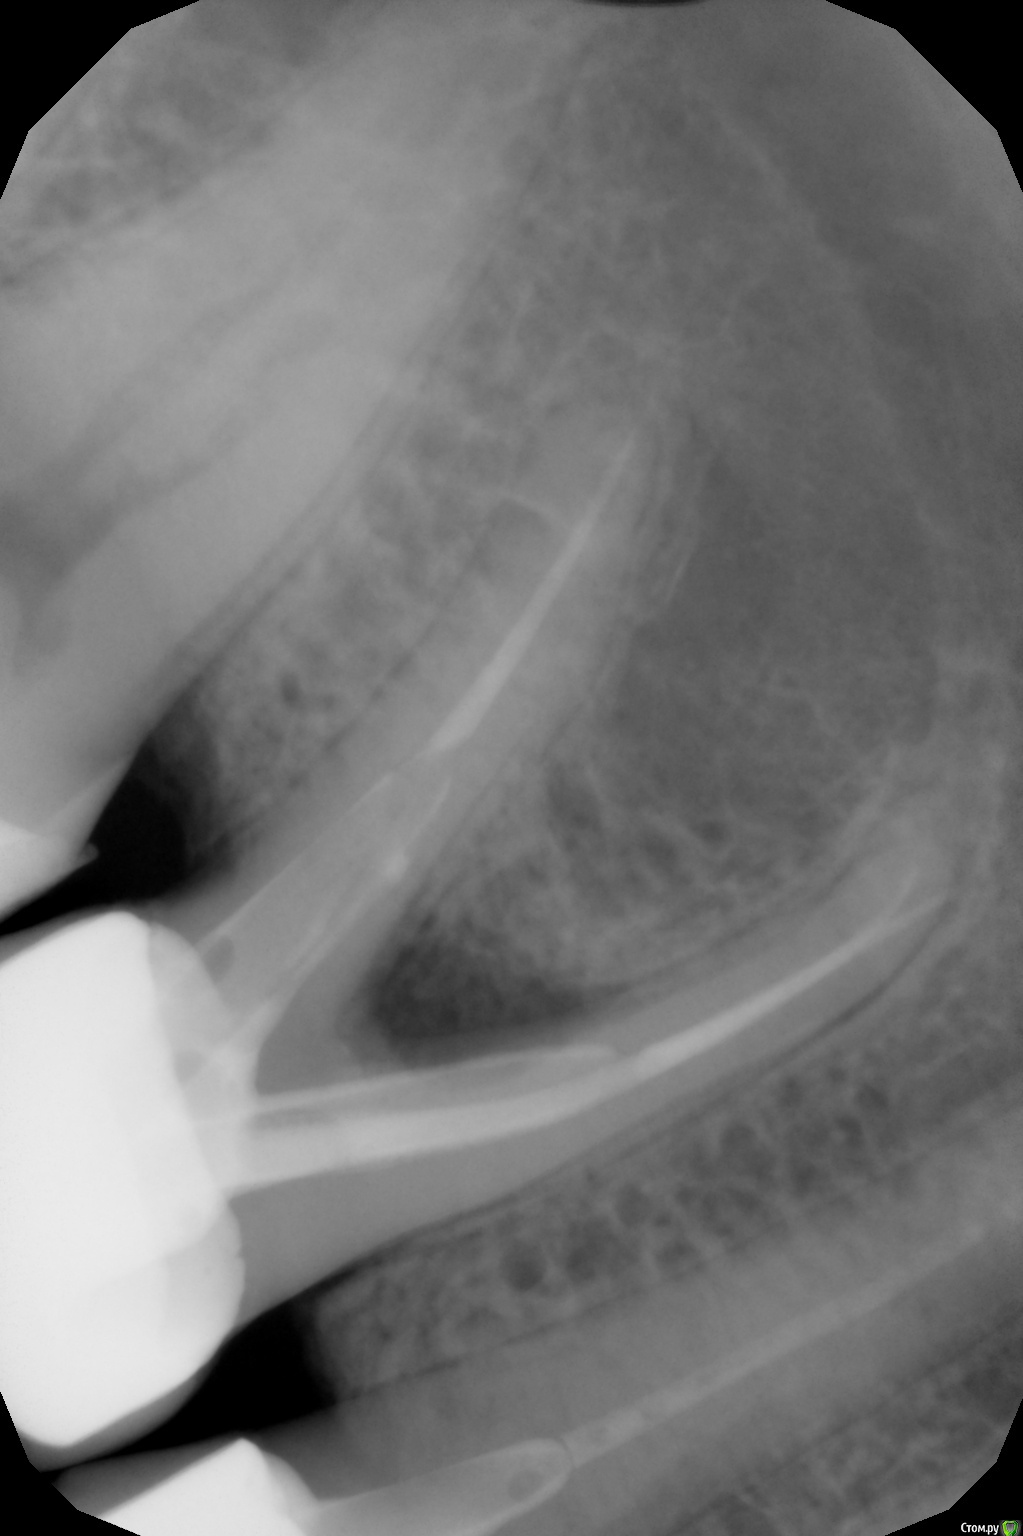

Irina231280 Опубликовано 3 августа, 2017 Автор Поделиться Опубликовано 3 августа, 2017 Прислали снимок. Посмотрите, пожалуйста. Ссылка на комментарий

red_butler Опубликовано 3 августа, 2017 Поделиться Опубликовано 3 августа, 2017 Зуб нужно удалять 1 Ссылка на комментарий

red_butler Опубликовано 4 августа, 2017 Поделиться Опубликовано 4 августа, 2017 Почему, объясните, пожалуйстаПоражена межкорневая область Ссылка на комментарий

Irina231280 Опубликовано 4 августа, 2017 Автор Поделиться Опубликовано 4 августа, 2017 Поражена межкорневая областьСпасибо! А почему она поражена, из-за чего? Трещина или перелом корня? Или по снимку это не понятно? Ссылка на комментарий

red_butler Опубликовано 4 августа, 2017 Поделиться Опубликовано 4 августа, 2017 Спасибо! А почему она поражена, из-за чего? Трещина или перелом корня? Или по снимку это не понятно?это уже не важно 1 Ссылка на комментарий